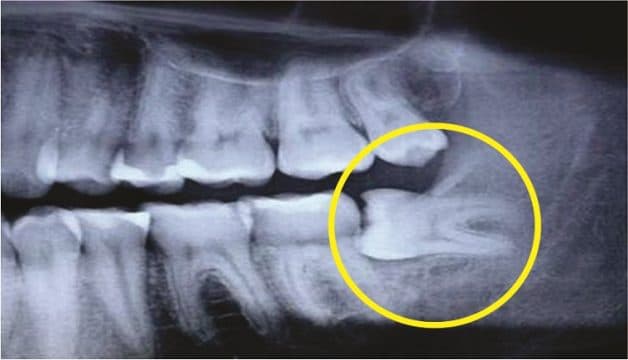

Răng khôn (răng số 8, răng hàm thứ 3) là loại răng cuối cùng mọc lên khi các răng vĩnh viễn đã phát triển đủ. Chính vì vậy, răng khôn được có xu hướng mọc lên theo nhiều hướng bất thường như mọc lệch gần, kẹt thẳng đứng, lệch phía sau, mọc ngang, kẹt trong niêm mạc và kẹt trong xương hàm. Điều này không chỉ gây ảnh hưởng đến những răng xung quanh mà còn có nguy cơ ảnh hưởng nghiêm trọng tới sức khoẻ. Chính vì vậy, đa số các trường hợp đều được bác sĩ chỉ định nhổ răng khôn để giúp loại bỏ triệt để tác hại do loại răng này gây ra.